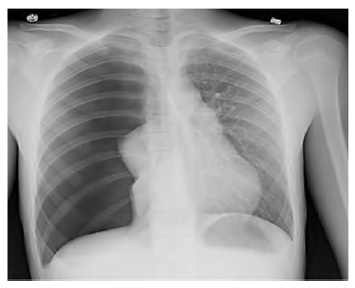

No que concerne a esse caso clínico hipotético, e considerando a imagem radiográfica apresentada, assinale a alternativa que indica, respectivamente, a hipótese diagnóstica e o tratamento para esse paciente.

Provas

Com base nesse caso clínico hipotético e na imagem radiográfica apresentada, e considerando os conhecimentos médicos correlatos, assinale a alternativa correta.